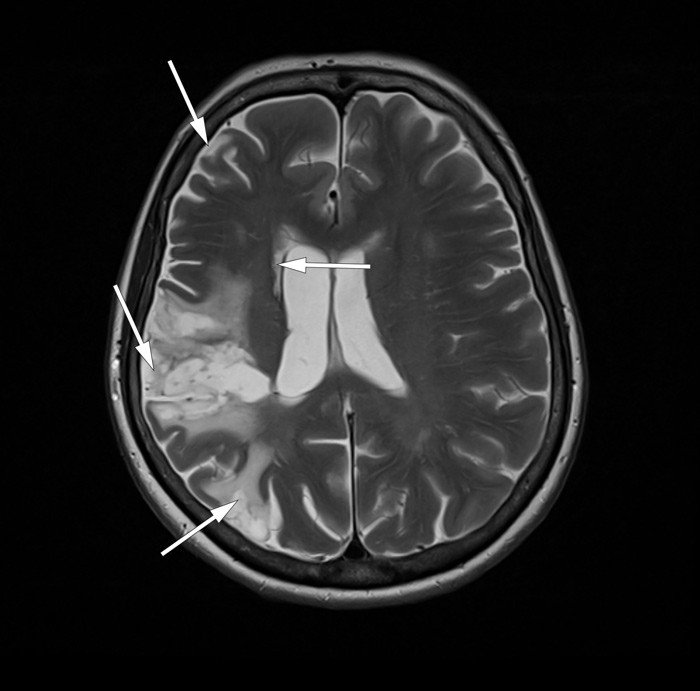

De to første årene etter dette akutte hjerneinfarktet hadde hun multiple transitoriske iskemiske anfall (TIA) og flere MR-bekreftede spredte infarkter i høyre hemisfære (bilde kun i nettutgaven), til tross for platehemmende og antikoagulerende behandling. Hun utviklet dysartri, venstre facialisparese og venstresidige sensimotoriske utfall. Grundig utredning inkludert ultralyd precerebrale halskar og CT-angiografi avdekket i denne perioden ikke embolikilde.